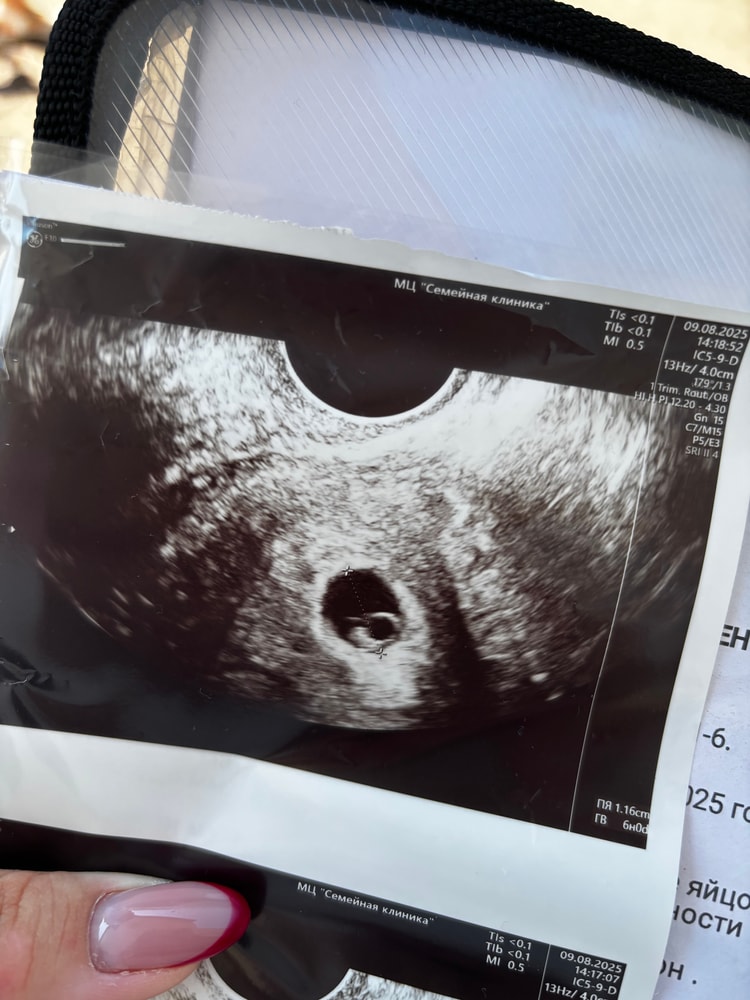

Узи 6+2

Сейчас на отдыхе в Геленджике, вчера немного помазало. Внепланово пошла на узи. И как же оно меня порадовало! Пуговка растет! Сердечко определяется. Ктр 5 мм, что соответствует 6+1. Какой сегодня чудесный день!